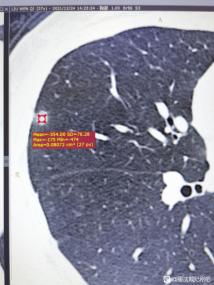

戴主任您好,我相信没有人喜欢在网上暴露自己的疾病,诉说自己的无助,但是恐惧、无助、不解,真的会摧毁一个人所有的尊严。在三个月前偶然体检,体检出纯磨玻璃结节5*6mm,-359hu。三个月之后湘雅做ct,已经变成了7*7mm混合磨玻璃结节,怀疑4b类,并且多发良性小结节。其实直到现在,我都很难接受,觉得自己拖累家人,拖累新婚的老公,我不抽烟不喝酒,也不知道为什么这个病能找到我。

按理来说,今年的元旦应该是非常幸福的,因为我所在的湖南下雪了。作为一名四川人,第一次在城里看到下雪,还在跟老公堆雪人、打雪仗。但当我拿到自己的ct报告单时,犹如一盆冷水直接浇到了我的头上:双肺多发小结节,右中肺7×7mm混合磨玻璃结节,纵膈见团片状阴影,大概2.1cm×1.3cm。